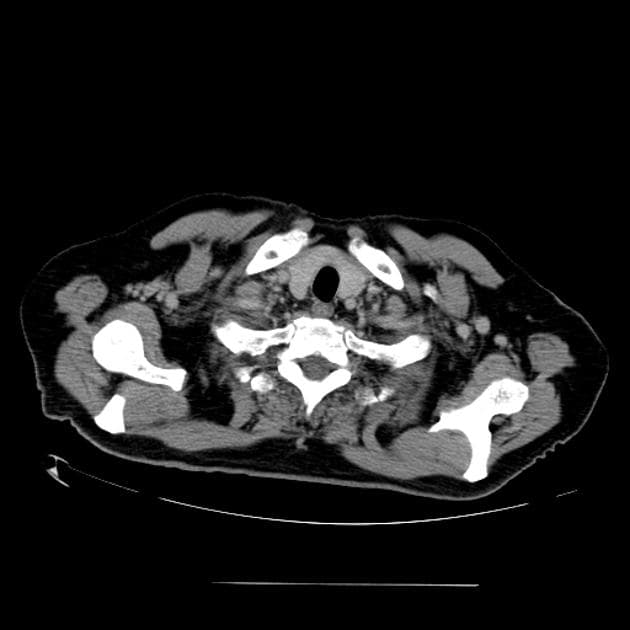

- Trên chụp CT sọ não có tiêm thuốc tương phản, thấy ngấm thuốc màng não mềm (leptomeningeal enhancement) và các nốt bắt thuốc (enhancing nodules) chủ yếu ở các bể nền (basal cisterns). Những hình ảnh này biểu hiện viêm màng não thể nền ưu thế (basal cistern predominant meningitis) kèm theo nhiều lao sợi (tuberculomas).

- Giãn cả hai não thất bên (both lateral ventricles) và não thất III (third ventricle), trong khi não thất IV (fourth ventricle) không giãn. Khi quan sát kỹ hơn, các tổn thương bắt thuốc (enhancing lesions) đang làm tắc lỗ ống nước (foramen aqueduct). Các hình ảnh này gợi ý giãn não thất do tắc nghẽn liên quan đến lao sợi (tuberculoma-related obstructive hydrocephalus).

- Các vùng giảm tỷ trọng (hypoattenuating areas) ranh giới không rõ ở cả hai nhân đuôi (caudate nuclei) gợi ý các vùng nhồi máu thể gai-đùi (lenticulostriate infarcts) do viêm mạch máu (vasculitis).

- Không thấy ngấm thuốc quanh não thất (periventricular enhancement) để gợi ý viêm não thất (ventriculitis).

- Không có bằng chứng của tập trung dịch bắt thuốc dạng viền (ring-enhancing fluid collection) để gợi ý áp xe (abscess formation).

- Không có dấu hiệu huyết khối xoang tĩnh mạch (venous sinus thrombosis).

- Không có dịch tích tụ ngoài trục não (extra axial fluid collection) để gợi ý áp xe dưới màng cứng (subdural empyema).

- Khuyết xương (bone defect) ở xương trán phải và các thay đổi thoái hóa hình thành sẹo (gliosis changes) ở thùy trán phải (right frontal lobe) là bằng chứng của việc đã từng đặt ống dẫn lưu ngoại não thất (extraventricular drainage tube) trước đó. Phần còn lại của vỏ sọ (calvarium) bình thường.

- Không có bằng chứng nhiễm trùng ở hòm nhĩ (tympanic cavities) và các tế bào khí nhĩ (mastoid air cells).